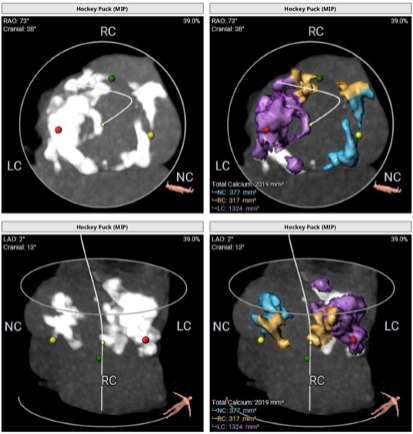

2)患者主动脉根部结构复杂,为Type 2型二叶瓣畸形,左右对合缘、右无对合缘处均可见钙化融合嵴,瓣环平面可见严重钙化,左冠窦底钙化灶延伸至左室流出道,且左室腔小。

瓣叶钙化严重,且增厚增长。

因患者自身主动脉根部结构特殊,导致定位困难:严重的钙化灶使得猪尾导管很难送至窦底;但凭借Evolut PRO稳定的多次可回收功能,术者通过对瓣膜的回收及再释放,最终找到最佳释放位置,获得最佳疗效。